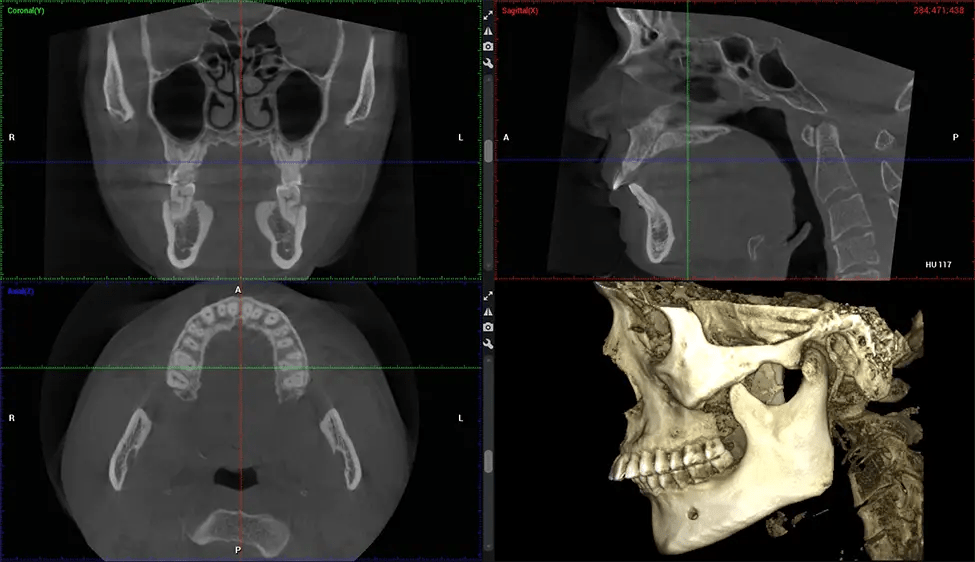

Full Skull to C7 of the Spine

There are many benefits to using CBCT technology, especially compared to the traditional 2D X-ray format. One of the most significant advantages of CBCT scans is that they provide much more information than traditional X-rays. A scan lets your dentist see images from all angles of your jaw and mouth, including your sinuses, nasal cavity, cheekbones, and other surrounding areas. This added information helps your dentist craft a comprehensive treatment plan that addresses all aspects of your oral health.

Planmeca Viso G7 CBCT ( Cone Beam CT Scan ) is designed to surpass the demands of industry leaders, specialists, and large institutions. It’s has a large ø25×30 cm sensor with four built-in cameras. It can capture unlimited volume sizes from a ø3×3 cm to a ø30x30cm volume capturing the skullcap through C7 on the cervical spine. The Planmeca Viso G7 offers the industry’s largest single volume scan of ø30×19 cm. It’s poised to handle advanced imaging modalities such as Planmeca ProFace® and Planmeca 4D™ Jaw Motion technology. The occipital head support allows an unimpeded view of facial tissue.